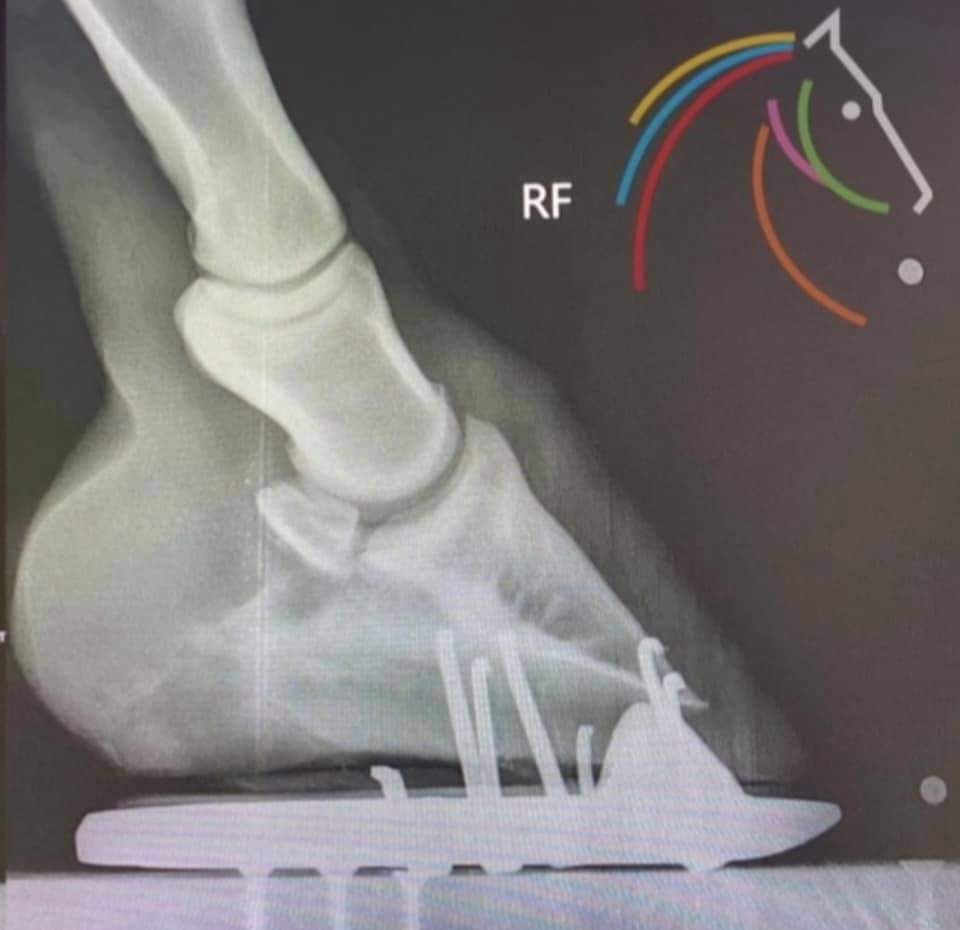

Bilden nedan är ett annat exempel.

Här ser vi hur mjukdelarna bak i hoven växer när dem får möjlighet att belastas (utan hindrande järnsko) samtidigt som andra delar på hoven verkats bort och kan få hoven att se mindre ut. Men hela hoven har inte blivit mindre. 😊

Från Equi Logical Lifestyle’s Instagram